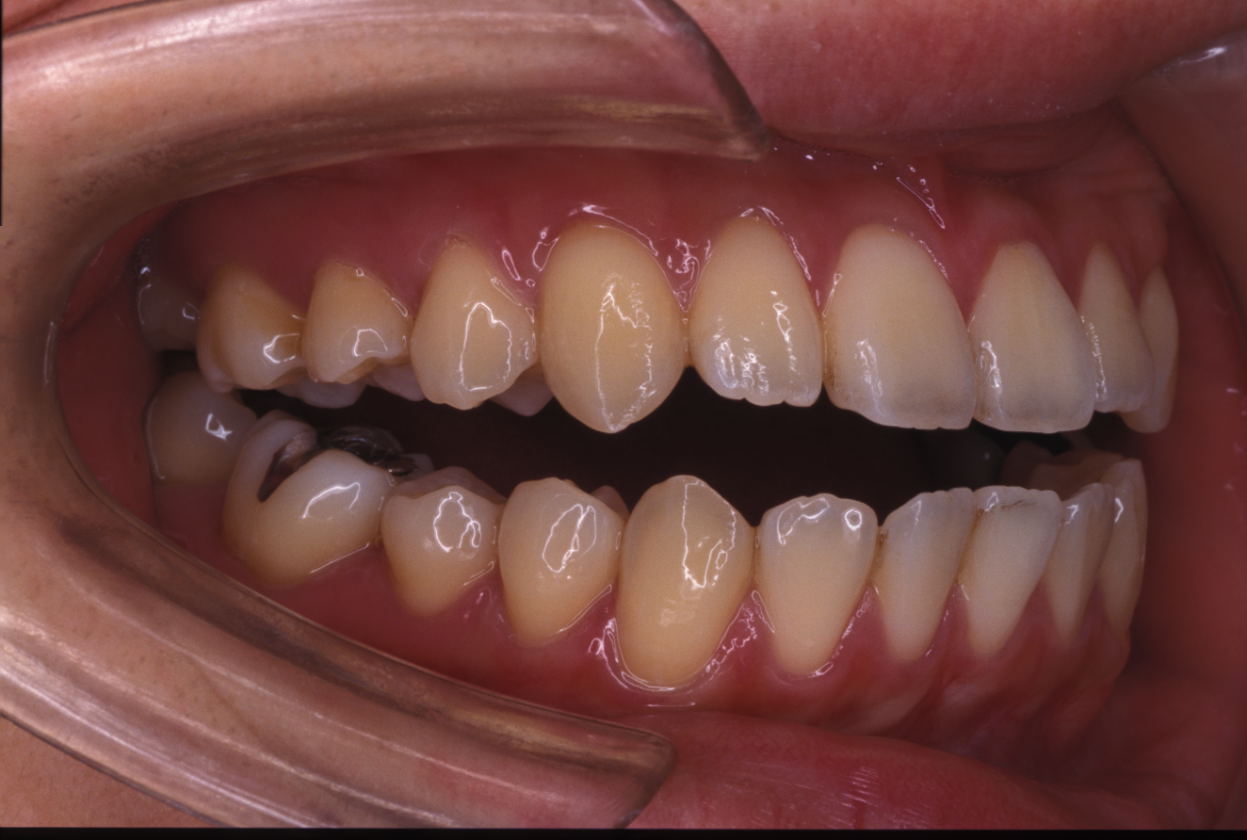

ほとんどの人が「開咬」と言うとき、それは前方の開咬を指します。前歯が開いている人は、上と下の前歯が外側に傾斜しているため、口を閉じたときに歯が接触しません。

開咬は不正咬合の一種で、顎を閉じたときに歯が正しく並んでいないことを意味します。

- スピーチ。開咬は会話や発音に支障をきたす可能性があります。たとえば、開咬の人の多くは舌足らずになります。

- 食べること。オープンバイトになると、食べ物を適切に噛んだり咀嚼したりすることができなくなります。

- 歯の磨耗。奥歯が噛み合う回数が増えると、摩耗により不快感や、歯の破折などのその他の歯の問題が発生する可能性があります。